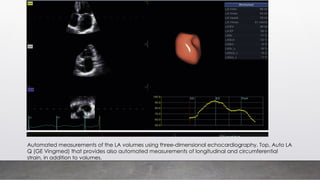

Automated measurements of the LA volumes using three-dimensional echocardiography. Top, Auto LA

Q (GE Vingmed) that provides also automated measurements of longitudinal and circumferential

strain, in addition to volumes.